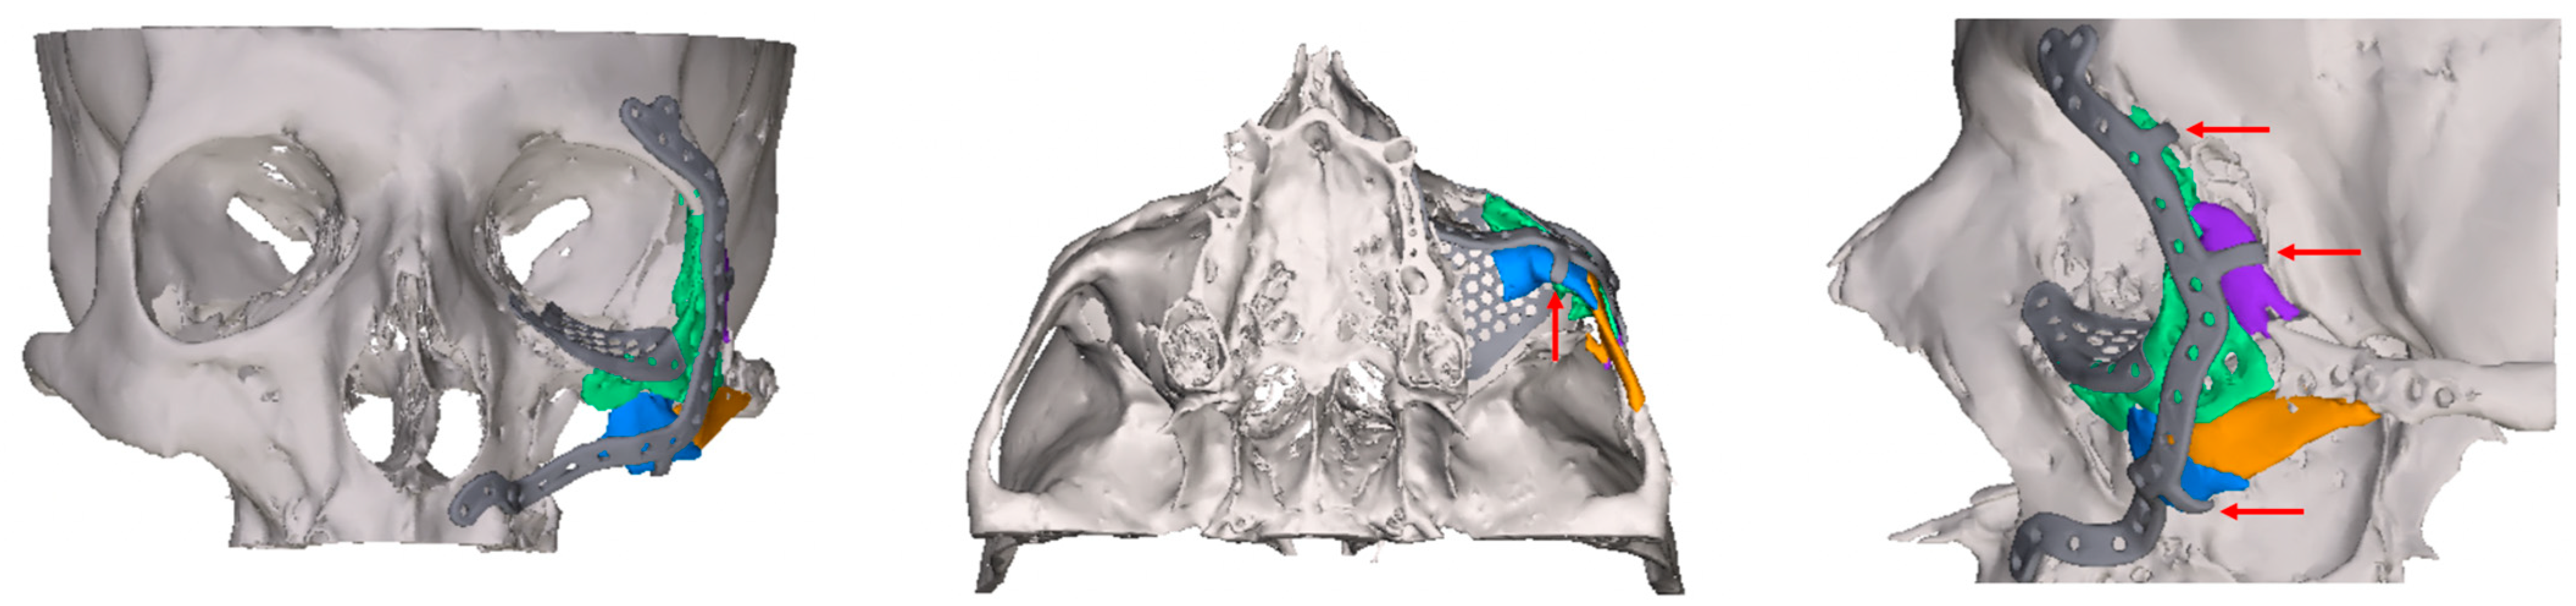

2.2. Digital Workflow and Implants

- Exposure of the fixation screws (infraorbital recess of the maxillary sinus) and limited exposure of the PSI (transition zone, ethmoid cells) without signs of mucosal swelling in these regions (n = 6 each)

- (Basal) mucosal swelling in the maxillary sinus indicative of chronic maxillary sinusitis, irrespective of the complexity of the primary injury (n = 4)

- Bone apposition at the PSI as a sign of osseointegration (n = 16)

- Remodeling of the dislocated bone fragments of the orbital walls (n = 16), including in the area of the infraorbital canal.